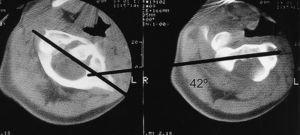

Paciente varón de 9 años con tortícolis asociada a fractura de clavícula por una caída en gimnasia. Tratado en su ciudad de origen mediante vendaje en 8 para la fractura de clavícula, y relajantes musculares y fisioterapia, fue remitido a nuestro centro a las 15 semanas por persistencia de la sintomatología (fig. 1). Las radiografías eran poco demostrativas, por lo que se practicaron estudios mediante TAC y RMN diagnosticándose de SRCAA tipo I3, con una divergencia C1-C2 de 42° (fig. 2); se instauró tracción halo-gravedad progresiva hasta un peso de 7 kg, en que se detuvo por aparición de disartria (17 días de tracción), con una movilidad rotacional levemente disminuida, la TAC de control mostró una divergencia residual de 11°, por lo que para evitar la recidiva se efectuó un artrodesis posterior C1-C2 in situ con injerto de cresta ilíaca (fig. 3), manteniendo la tracción durante la intervención e inmovilizándose con halo-yeso 3 meses. Una vez retirada la tracción, la disartria remitió espontáneamente. Quince años después, el paciente presenta una movilidad cervical prácticamente normal, con una limitación de la rotación izquierda de 10°.

Figura 2. Imagen de la tomografía axial computarizada (TAC) del paciente n.O 1 que muestra el método de medición, con una divergencia atlanto-axial de 42°.